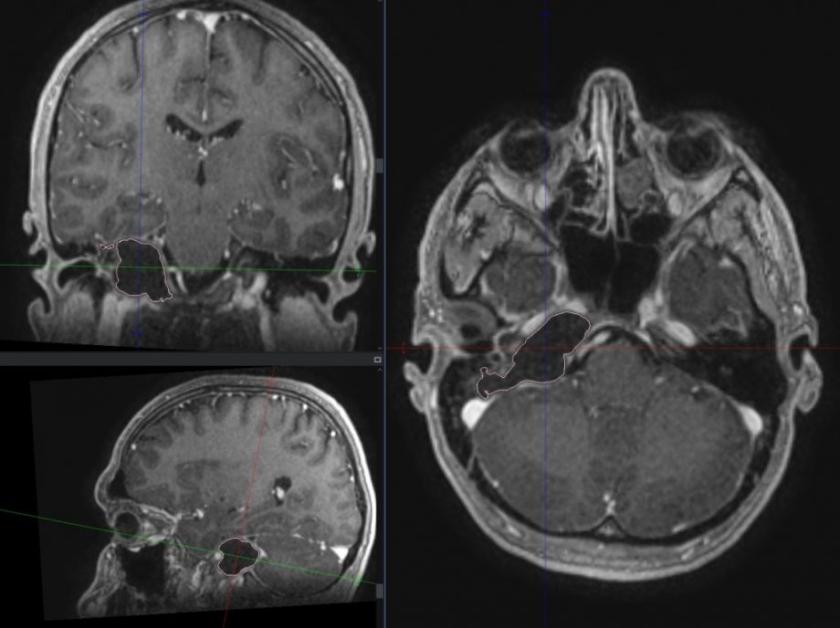

În premieră, medicii specialiști neurochirurgi de la Institutul de Medicină Urgentă au operat cu succes o tumoră de bază craniană profundă. Pacientul chiar din prima zi postoperator a reușit să se deplaseze și nu a prezentat deficit neurologic adițional. A fost externat din spital după cinci zile de la intervenție.

Pacientul care a fost operat este un bărbat de 40 de ani, diagnosticat cu tumoră gigantă de bază craniană profundă cu extindere în apexul petros, urechea internă și fosa posterioară.

Pacientul a fost supus intervenției neurochirurgicale în Departamentul de Neurochirurgie din cadrul IMSP Institutului de Medicină Urgentă de înlăturare în totalitate a tumorii. Intervenția a fost posibilă atât datorată experienței echipei neurochirurgicale și neuro-anesteziei cât și tehnicii folosite intraoperatorii (microscop performant, drill cu viteză înaltă, neuronavigație). Durata intervenției a fost de patru ore.